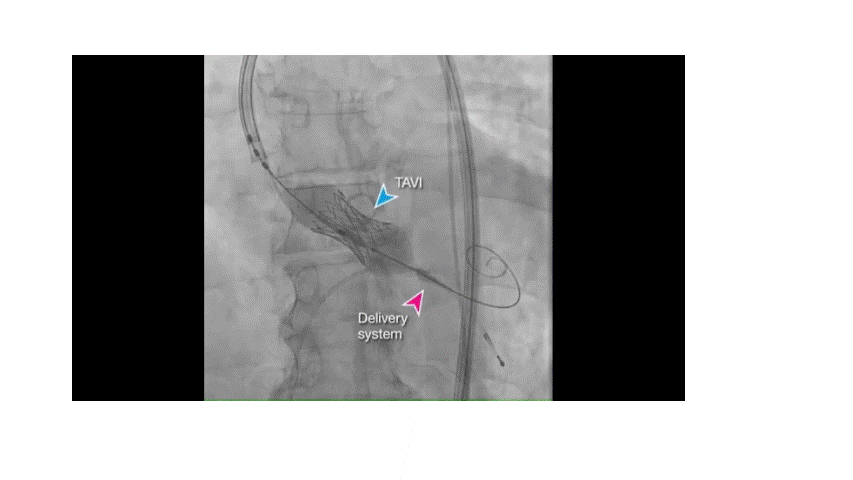

AV loop is not mandatory. In modern delivery systems and softer, trackable sheaths, several groups report successful direct antegrade closure without creating a loop. This is feasible in: Small to moderate VSDs When the defect is straight and easily crossed .The popular series from Dr .K.Sivakumar & team from Madras medical mission Chennai, India (Ref 1)

Image source :Ref 1

- Sagar P, Thejaswi P, Garg I, Singh D, Pradeep A, Dutt N, K.Sivakumar et al. Transcatheter closure of ventricular septal defects by exclusive transvenous antegrade cannulation from the right ventricle: a 5-year retrospective cohort study. https://doi.org/10.1101/2024.05.28.24308078.